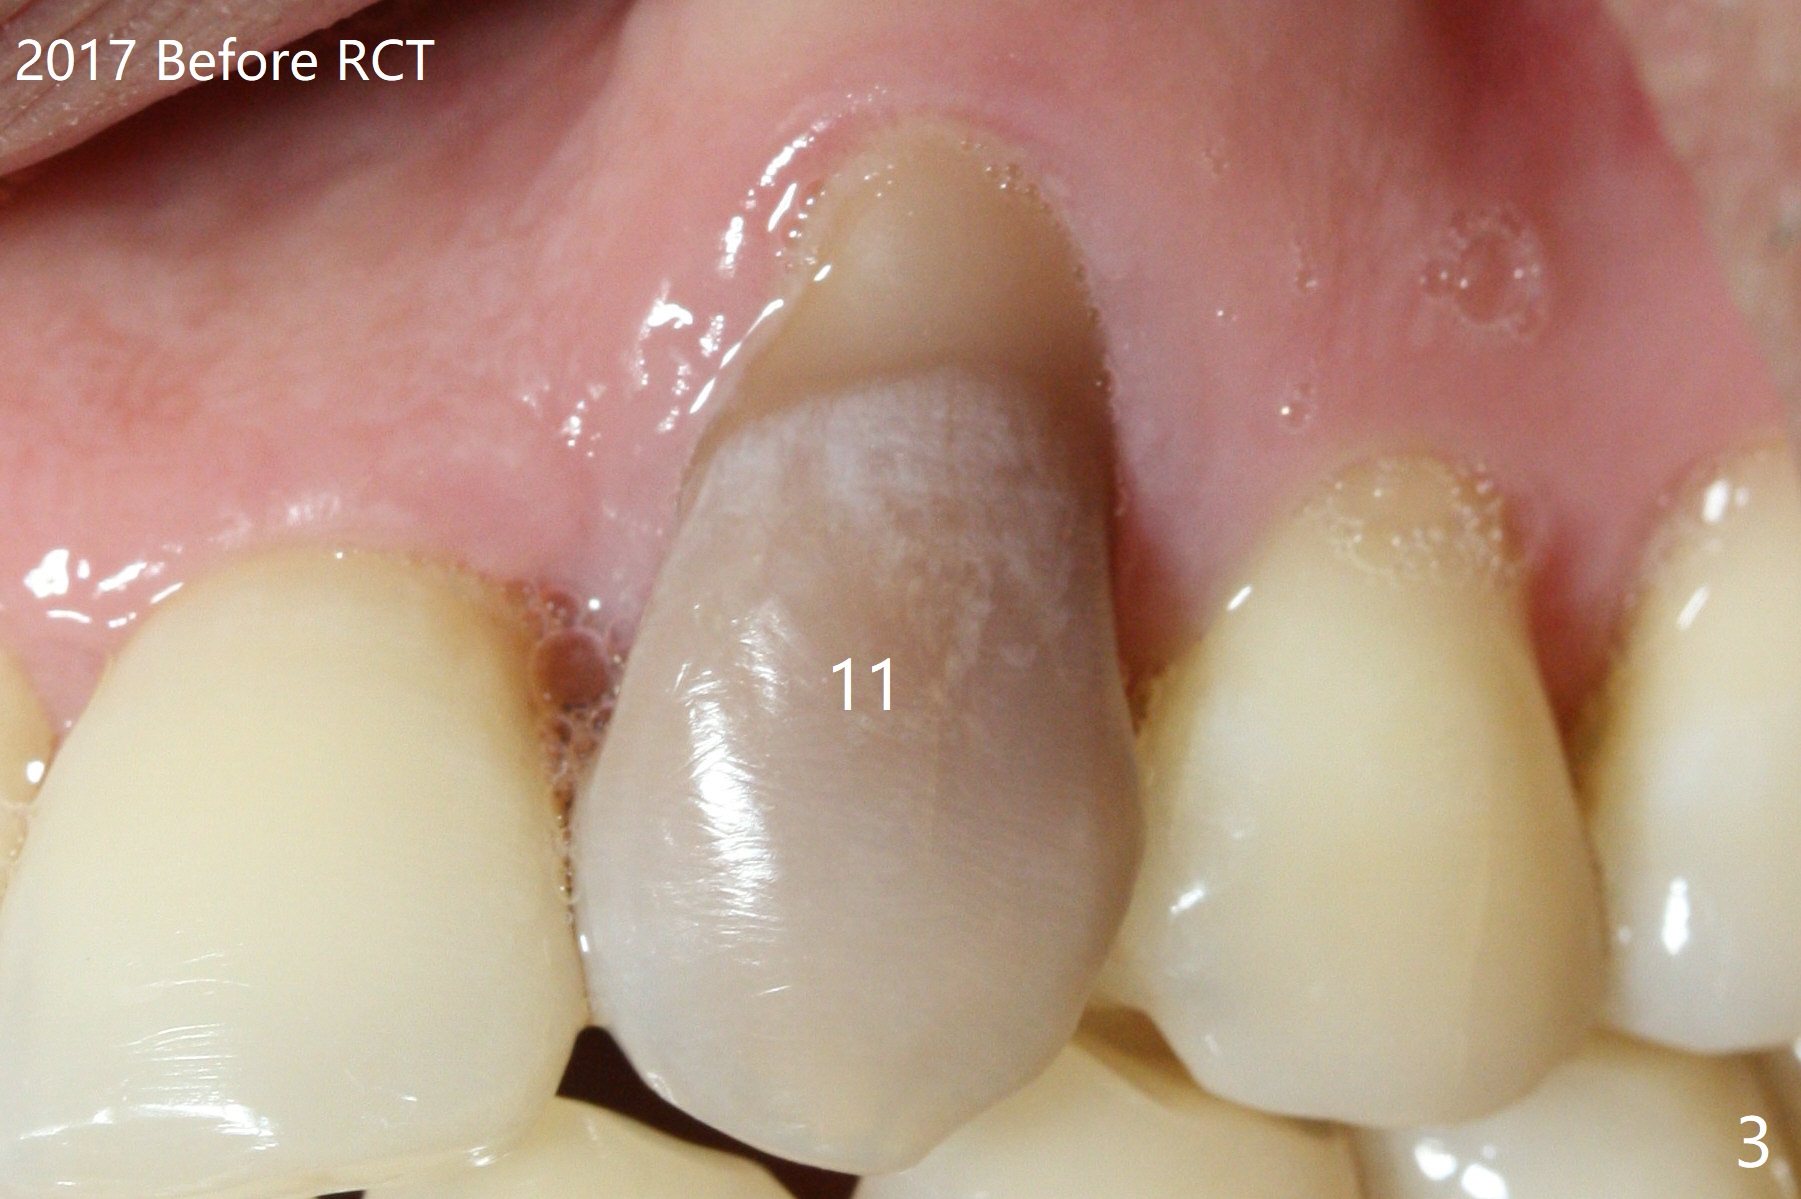

A 45-year-old man had severe malocclusion and chose non-extraction orthodontic treatment (Fig.1 (2012)). Five years later, the tooth #11 discolors (Fig.3, as compared to #6 in Fig.2). Immediately after RCT (Fig.4,5), the affected tooth has sudden change in shade (Fig.6). Two weeks later there is rebound in shade (Fig.7). The latter improves after two rounds of chair-side internal bleaching with 35% Hydrogen Peroxide for 20 minutes and build-up with the lightest shade composite (Fig.8). For optimum, place the bleach gel in the pulpal chamber and close the access with Cavit for a few days. In fact the latter is unnecessary. The treated tooth looks as normal as the tooth on the other side 1 year 10 months post whitening (Fig.9). PARL reduces 3 years post RCT (Fig.10 <, as compared to Fig.5).